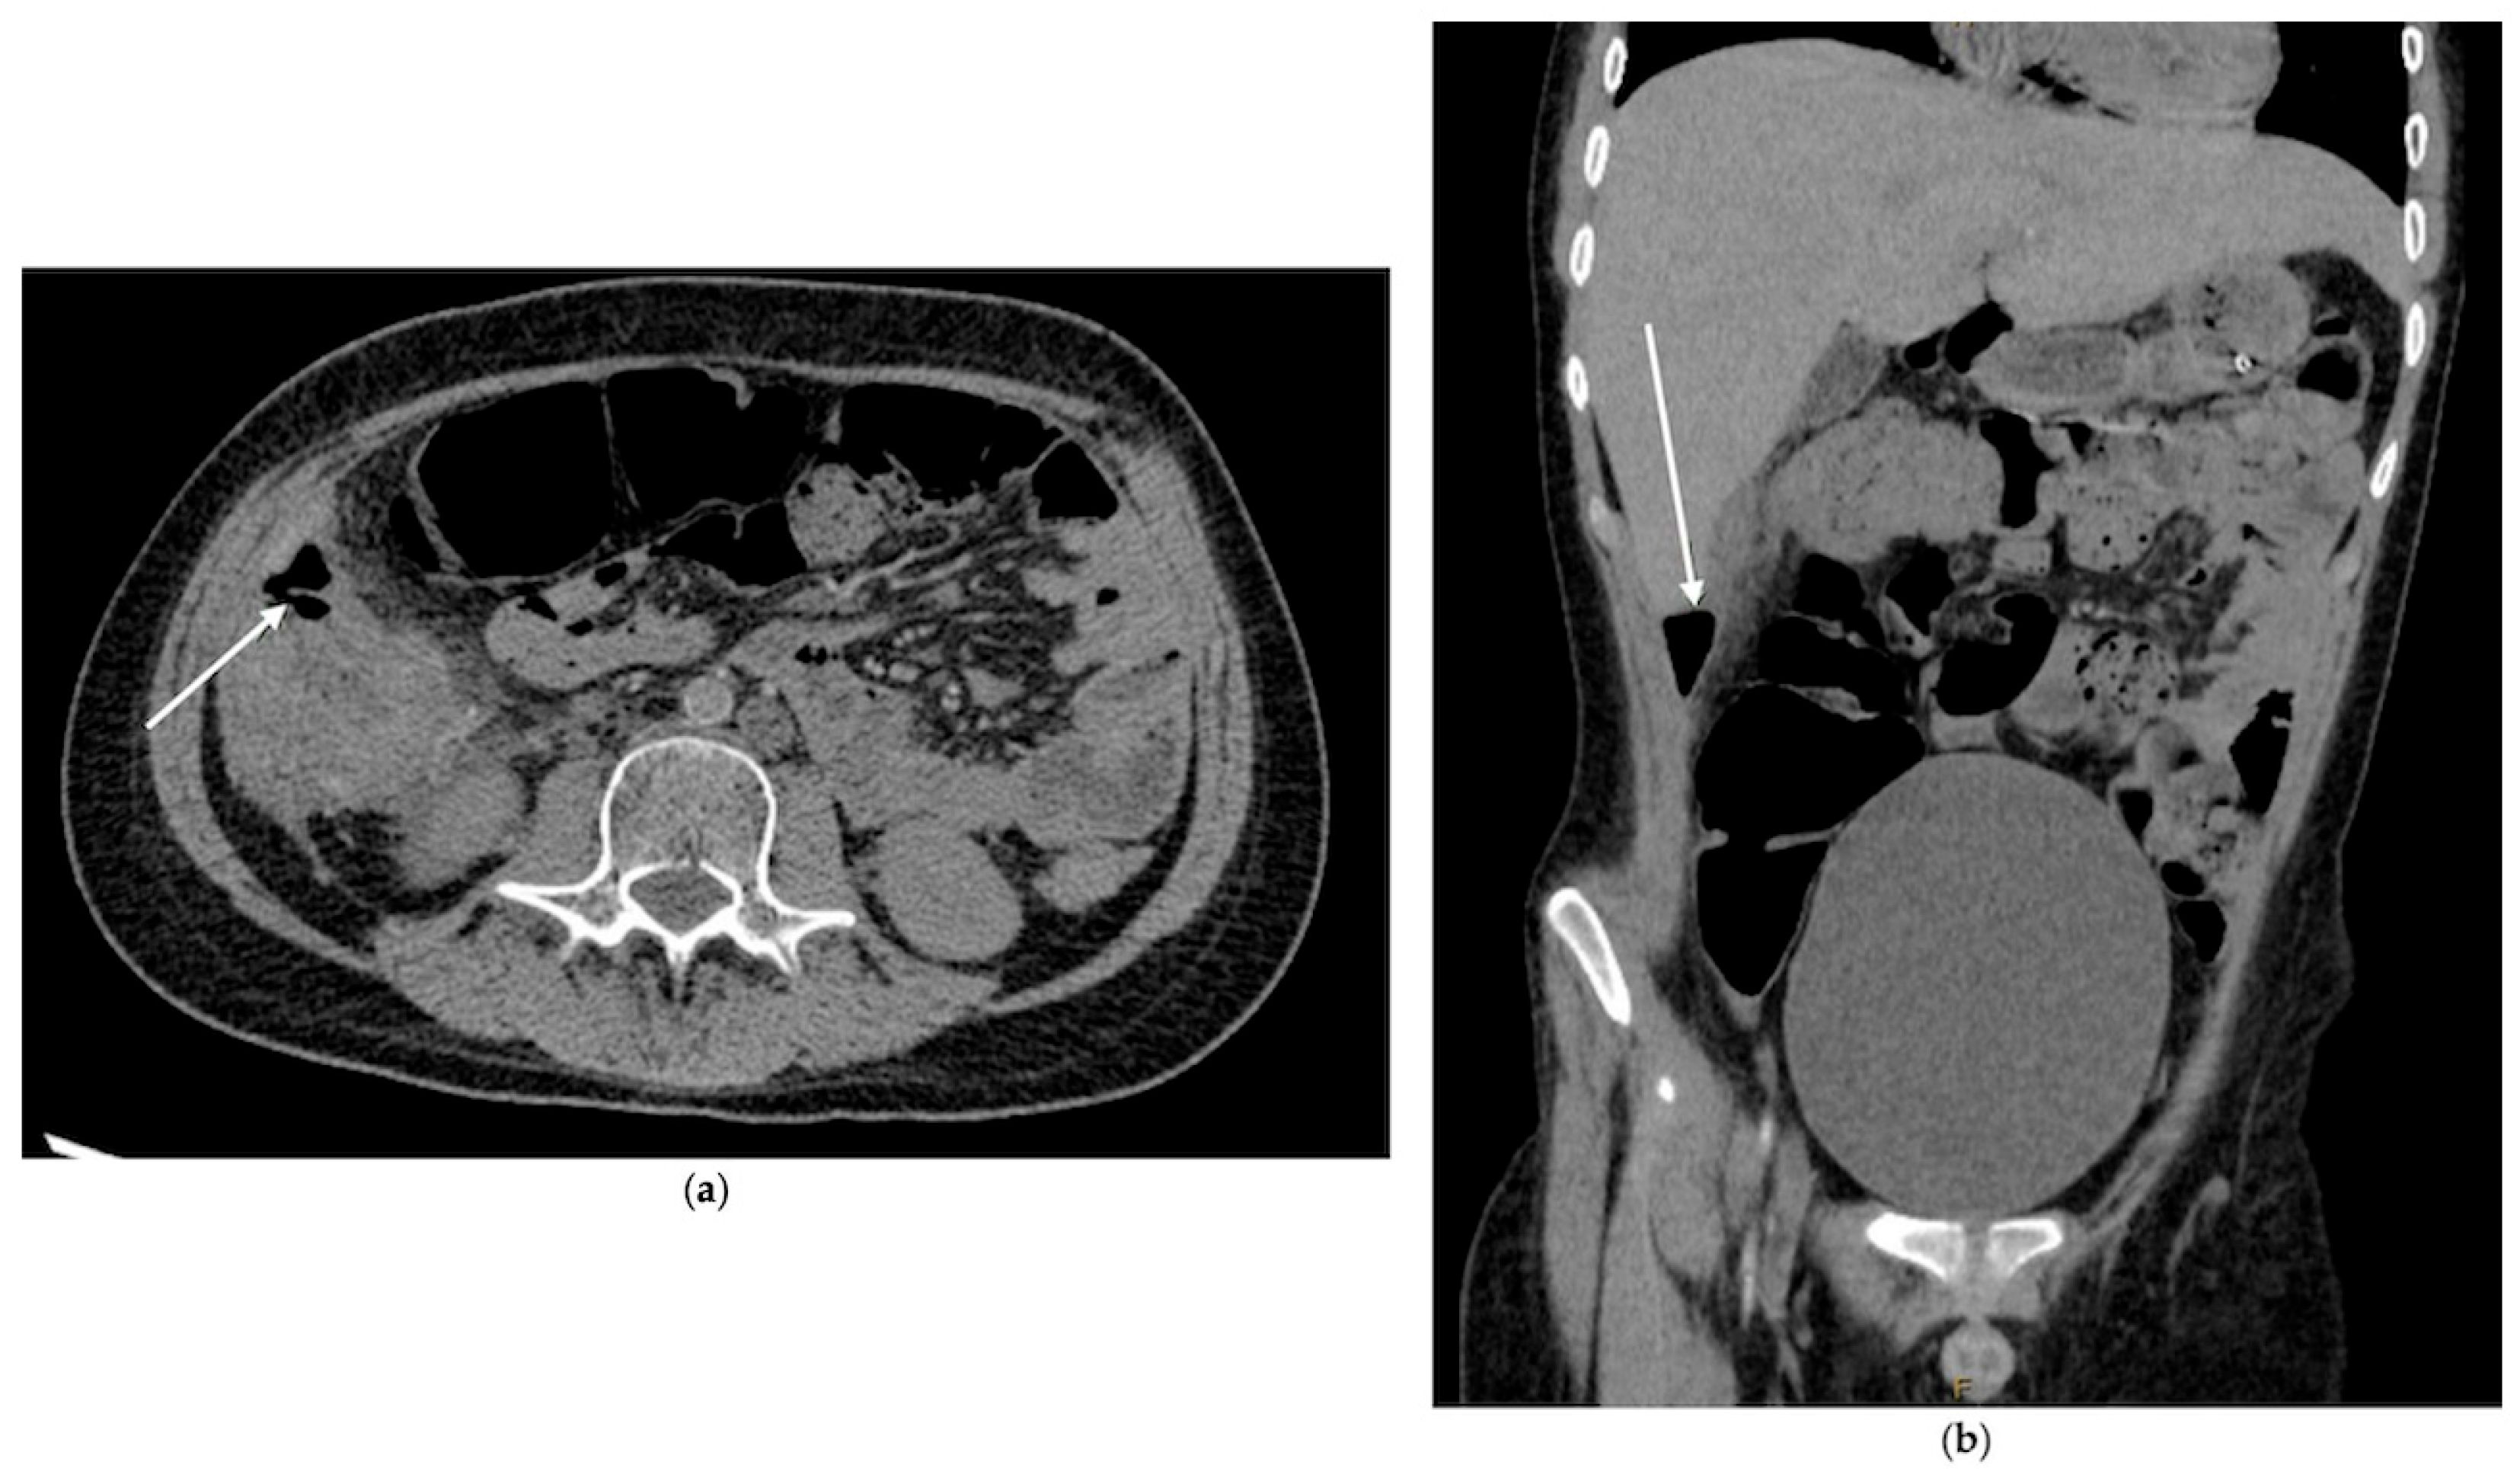

2.1.1. Case 1

2.1.2. Case 2

2.1.3. Case 3

- Incidental imaging clues: Retrospective analysis identified free air in two cases, underscoring that radiographic “soft signs” must be taken seriously in this context.

- Quick and Thorough Imaging: Be ready to order detailed abdominal imaging (such as a CT scan) for any concerning gastrointestinal symptom. A team of specialists should carefully review the images, as subtle signs, such as tiny pockets of air or changes in the bowel wall, can be missed.